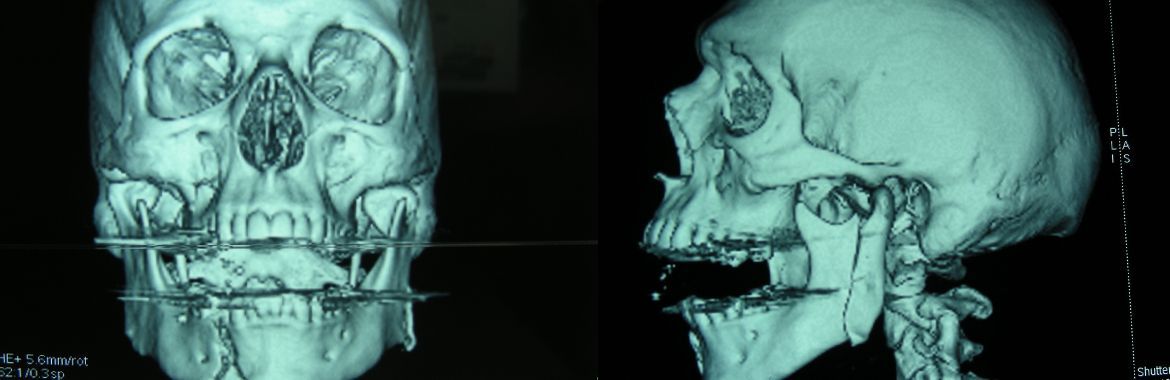

Traumatologie

Behandlung von Weichteilverletzungen/ Frakturen im Mund-, Kiefer-, Gesichtsbereich ambulant in der Praxis oder im Rahmen der Belegarzttätigkeit am Spitalzentrum Biel in Narkose.

- Unterkieferfrakturen

- Mittelgesichts-, Augenbodenfrakturen